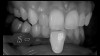

(14.) Photograph of fractured right lateral incisor taken with a smartphone and an EALS device during patient presentation for emergency treatment shown with accompanying radiograph.

Figure 14

(15.) Photograph of fractured right lateral incisor taken with a smartphone and an EALS device during patient presentation for emergency treatment shown with accompanying radiograph.

Figure 15

Emergency Care and Referral to Specialists

Emergency visits are a common and unpredictable occurrence at nearly all dental practices (Figure 14 and Figure 15). When an emergency occurs, the patient's provider may not always be available to evaluate and initiate treatment. In a similar manner, new patients of record frequently present with oral conditions that require the attention of a dental specialist who may only be available at another clinic (Figure 16 and Figure 17). For many of these patients, immediate access to care may be limited, and if a patient is experiencing discomfort, time will be a critical factor in regard to initiating a proposed plan of action. The use of a smartphone with an EALS can allow the clinical staff to rapidly acquire intraoral photographs or a video and transmit these images and other information via encrypted text message or secure e-mail to anywhere in the world for immediate consultation. The combination of telecommunications and dentistry is known as teledentistry,13which has been shown to impart significant benefits to patients and providers in the fields of oral medicine,14 oral and maxillofacial surgery,15 endodontics,16 prosthodontics,17 periodontics,18 pediatrics,19 orthodontics,20 and oral hygiene.21